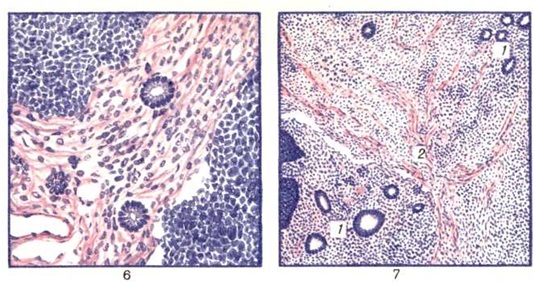

Опухоль имеет вид хорошо отграниченного узла и может достигать больших размеров (рисунок); располагается под капсулой или около ворот почки. Опухоль плотная, на разрезе чаще имеет вид гомогенной ткани, серого или розового цвета, иногда пёстрая. Гистологически (цветной рисунок 6 и 7) выделяют: 1) опухоли с преобладанием нефрогенной ткани, которые могут быть с выраженной дифференцировкой нефрогенного зачатка, со слабо выраженной дифференцировкой нефрогенного зачатка, с недифференцированным нефрогенным зачатком; 2) опухоли с преобладанием мезенхимальной ткани; 3) опухоли с преобладанием нейроэктодермальной ткани. Нефрогенная ткань в Вильмса опухоль напоминает эмбриональный зачаток почки и представлена скоплениями или тяжами мелких клеток с круглыми или овальными ядрами и узким ободком цитоплазмы. Клетки образуют трубочки, подобные почечным канальцам, или структуры, напоминающие почечные клубочки. Мезенхима опухоли состоит из круглых или звездчатых клеток, сходных иногда с фибробластами и свободно лежащих среди переплетающихся фиброзных волокон. Нейрогенная ткань представлена клетками, напоминающими симпатогонии и симпатобласты. Местами эти клетки образуют розетки или располагаются рядами, характерными для симпатобластомы. В Вильмса опухоль нередко встречаются комплексы из мышечных волокон и миобластов. В большинстве случаев опухоль бессосудистая; наиболее часто метастазирует в лёгкие, лимфатических, узлы, реже в печень, редко в другие органы. |